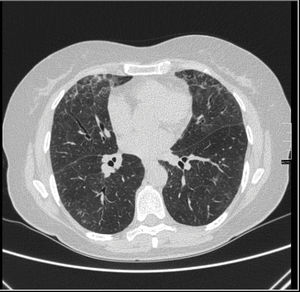

Se presenta el caso de una mujer de 62 años con historia de ITU de repetición, sin otros antecedentes. Se inició profilaxis con nitrofurantoína un año previo a la presentación de los síntomas. Remitida a reumatología por artralgias migratorias asimétricas de 4 meses, a la anamnesis refería disnea de moderados esfuerzos de aparición posterior a las artralgias. En la exploración física se auscultaban crepitantes bilaterales. La Rx de tórax mostró patrón intersticial bilateral, y en la tomografía computarizada de alta resolución (TACAR) áreas en vidrio deslustrado correspondientes a neumonía intersticial aguda/subaguda (fig. 1). En la analítica sanguínea destacaba GOT 360U/l, GPT 432U/l y GGT 279U/l con ecografía abdominal normal. La serología de virus hepatotropos y el estudio de anticuerpos de hepatitis autoinmune fueron negativos. En autoinmunidad se detectó ANCA+ 1/640 patrón perinuclear (anti-mieloperoxidasa y anti-proteinasa 3 negativos). Tras los hallazgos, se sospechó toxicidad por nitrofurantoína y se suspendió el fármaco. Se instauró tratamiento con prednisona, con buena respuesta a nivel respiratorio, descenso de enzimas hepáticas y resolución completa de artralgias. Durante su seguimiento los valores de transaminasas han permanecido normales, la clínica respiratoria desapareció y las pruebas de imagen pulmonares posteriores son normales. Las artralgias han remitido y los títulos de ANCA se han negativizado.

Existen reportes de casos de toxicidad pulmonar y hepática concomitante atribuida al uso de nitrofurantoína3. La toxicidad pulmonar como la hepática tienen 2 tipos de presentaciones: aguda y crónica. Los síntomas de toxicidad pulmonar crónica se desarrollan después de varios meses de tratamiento; los más comunes son disnea, tos irritativa y fatiga. Al examen físico suelen auscultarse crepitantes sobre todo en bases4. Existen anomalías radiográficas en la mayoría de pacientes, principalmente en campos inferiores y bilaterales. En la TACAR pueden observarse áreas de vidrio deslustrado, engrosamiento septal y bronquiectasias por tracción5.